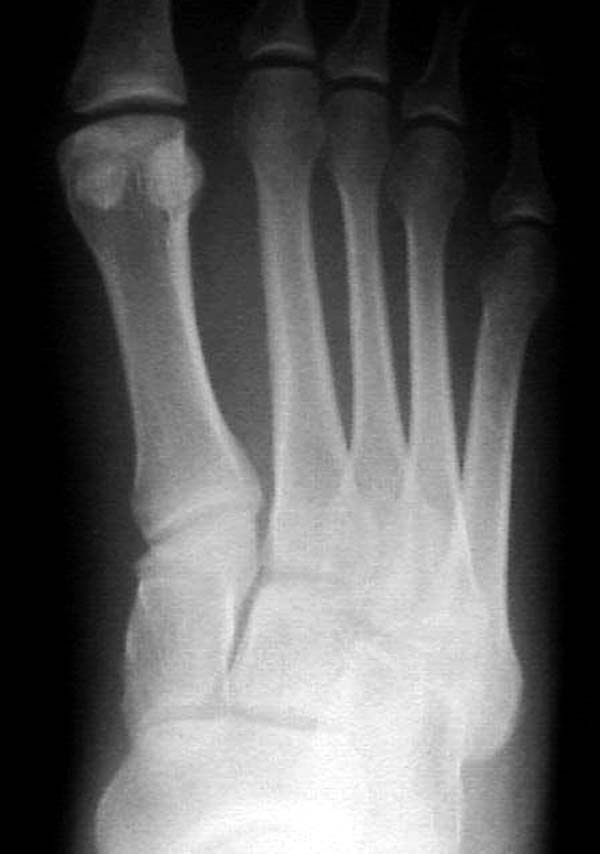

Ренген снимки прислал один из моих коллег из бывшего союза, просит совета. К нему в клинику обратился с жалобами 24 летний студент, получил травму две недели назад катаясь на скейтинг борд.

Ходить прихрамываясь на конечность. Небольшая отечность на тыле стопы, неврологических и сосудистых изменений нет. Подскажите, что предпринимать больному? Снимки представлены. Djoldas Kuldjanov, MD Department of Orthopedic Surgery St. Louis University Medical Center